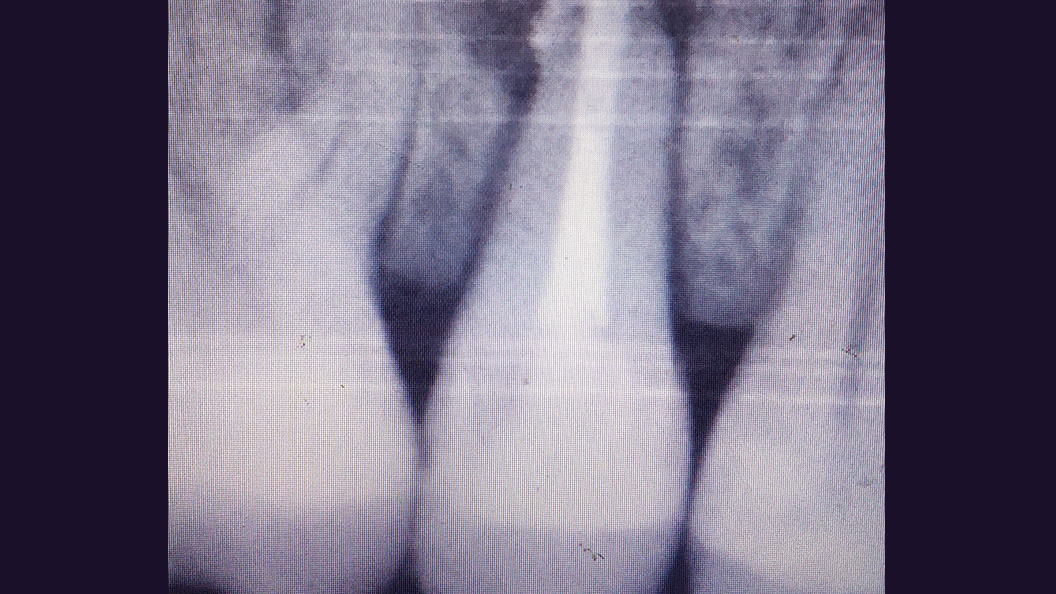

До и после лечения

В клинику обратился пациент с жалобами на постоянные ноющие боли и резкую боль при накусывании. С его слов, зуб ранее лечили в другом ЛПУ по поводу хронического фиброзного пульпита. После осмотра врач Черных Антон Алексеевич проанализировал рентгенограмму, поставил диагноз и провёл повторное эндодонтическое лечение зуба 1.5.

Перелечивание каналов необходимо при воспалении тканей, окружающих зуб. Требуется при попадании инфекции или при дефектах ранее проведённого лечения: недопломбированные участки, рассосавшийся пломбировочный материал внутри каналов.

В ходе лечения были проведены следующие работы:

- эндодонтическое лечение с применением коффердама

- постоянная пломбировка корневых каналов

- восстановление коронковой части зуба